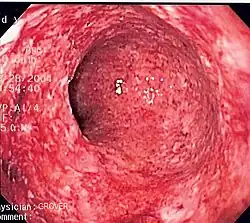

Endoscopy

A colonoscopy is the best test for making the diagnosis of Crohn's disease, as it allows direct visualization of the colon and the terminal ileum, identifying the pattern of disease involvement. On occasion, the colonoscopy can travel past the terminal ileum, but it varies from person to person. During the procedure, the gastroenterologist can also perform a biopsy, taking small samples of tissue for laboratory analysis, which may help confirm a diagnosis. As 30% of Crohn's disease involves only the ileum,[1] cannulation of the terminal ileum is required in making the diagnosis. Finding a patchy distribution of disease, with involvement of the colon or ileum, but not the rectum, is suggestive of Crohn's disease, as are other endoscopic stigmata.[134] The utility of capsule endoscopy for this, however, is still uncertain.[135] A "cobblestone"-like appearance is seen in approximately 40% of cases of Crohn's disease upon colonoscopy, representing areas of ulceration separated by narrow areas of healthy tissue.